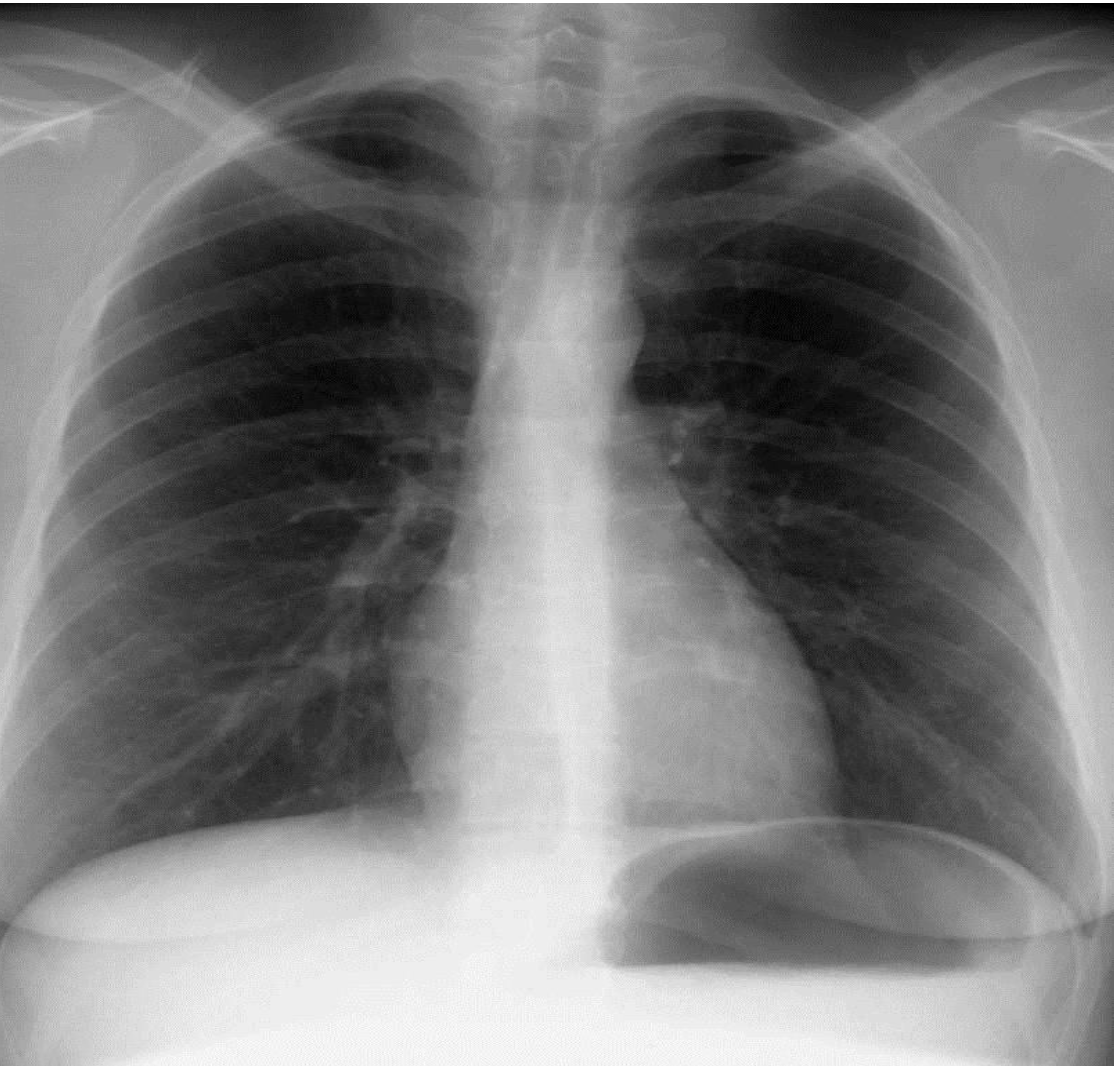

What it cardiac tamponade? Treatment

Inflammatory fluid leaks into the pericardial cavity and compresses on the heart! And limits its ability to pump blood!

Insert a stringe into the perocardial cavity amd drain excess fluid>> pericardiocentesis

Cardiac tamponade is compression of the heart leading to a fall in arterial blood pressure